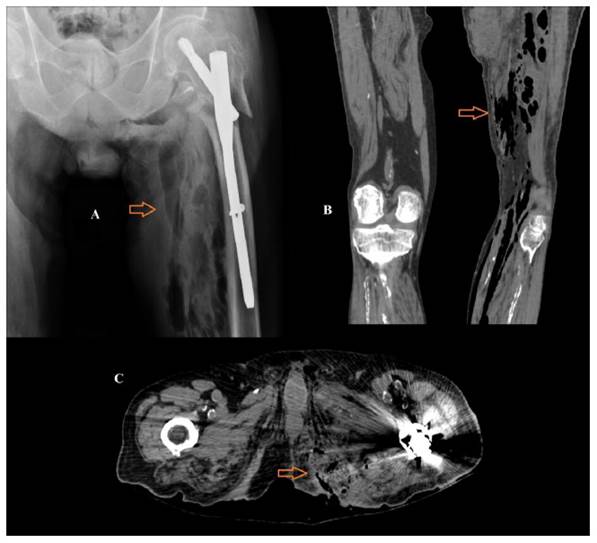

Se realizó una radiografía de la cadera izquierda y, ante la presencia de gas en el muslo, se completó con una Tomografía Computerizada (TC) de miembros inferiores, observando múltiples colecciones aéreas que afectaban a la fascia superficial, tejido subcutáneo y grupos musculares profundos del miembro inferior izquierdo, con origen en úlcera de decúbito retroisquiática izquierda y extensión caudal a los compartimentos descritos (Figura 1).

Con estos hallazgos, el paciente fue diagnosticado de fascitis necrotizante secundaria a úlcera por decúbito en región perineal. Se desestimaron actuaciones agresivas dado los antecedentes personales del paciente y la situación clínica del mismo, adoptándose medidas de confort. El paciente falleció a las pocas horas de su ingreso en Urgencias.

En las radiografías simples se puede apreciar aire en el interior de las partes blandas. En la TC, la presencia de colecciones aéreas con afectación de las fascias y los planos musculares es diagnóstica de fascitis necrotizante. También se ha descrito que la ausencia de realce de los planos fasciales tras la administración de contraste intravenoso es un signo radiológico que ayuda a distinguir entre fascitis necrotizante y no necrotizante cuando no se aprecien burbujas aéreas en el estudio sin contraste, lo que puede ocurrir en algunas ocasiones6.